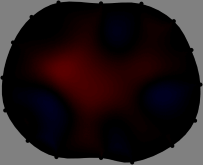

Figs. 3 and 4 compare the performance of the proposed FER method in (20) with the standard regularized least-squares method ((19) when \mathcal{R} is the identity matrix). The regularization parameter of the standard method was heuristically chosen for its best performance, and the parameter of the FER method was set to be one of three different values λ=0.05,0.2,𝜆0.050.2\lambda=0.05,0.2,\infty. The injection current was 1 mARMSRMS{}_{\tiny{\mbox{RMS}}} at 100 kHz, and the frame rate was 9 frames per second. The reference frame at t0subscript𝑡0t_{0} was obtained from the maximum expiration state. The measured data, 𝐕˙(tm)˙𝐕subscript𝑡𝑚\dot{\mathbf{V}}(t_{m}), represent the voltage differences between each time tmsubscript𝑡𝑚t_{m} and t0subscript𝑡0t_{0}. The blue regions, which denote where conductivity decreased by inhaled air, increased during inspiration and decreased during expiration. The FER method with λ=𝜆\lambda=\infty was clearly more robust than the standard method that produced more artifacts originated from the inversion process.

Figure 3: The reconstructed images of the conductivity change of the subject A by the standard regularized least square method and the proposed fidelity-embedded regularization (FER) method for three difference values λ=0.05,0.2,𝜆0.050.2\lambda=0.05,0.2,\infty. Here, the time step is 0.22 seconds (tm+2tm0.22subscript𝑡𝑚2subscript𝑡𝑚0.22t_{m+2}-t_{m}\approx 0.22).